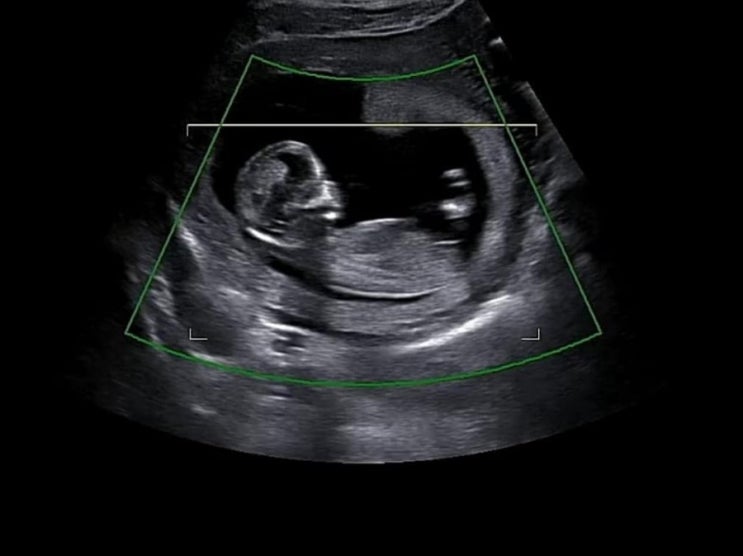

임신12주차/1차기형아검사, 입체초음파,목투명대 검사

#1차기형아검사 #입체초음파 #임신12주차 #목투명대 #투명대검사 기다리고 기다리던 4주가 지나가고 12주차...